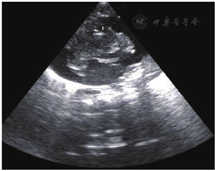

急查胸部X线片示PICC管端位于右心室内,导管远端弯曲(图1),急查心脏超声提示心室周围可见液性暗区包围,右室前壁心包腔内约5 mm(图2),左室后壁心包腔内液性暗区深约9 mm(图2),心包积液诊断明确,心包积液结果示:颜色乳白,透明度混,李瓦它试验阳性,细胞总数1 058×106/L,白细胞总数58×106/L,分类淋巴细胞0.13,分类中性粒细胞0.16,乳糜试验阳性,细菌培养阴性。血气分析提示:pH 7.03,PCO2 44 mmHg (1 mmHg=0.133 kPa),PO2 55 mmHg,BE-18.8 mmol/L, HCO3- 11.3 mmol/L,提示严重代谢性酸中毒。

患儿于PICC置管后3 d突然出现严重心动过缓及低血氧饱和度,听诊心音遥远,常规气管插管、心脏按压等抢救措施无效,行心脏超声提示:大量心包积液,胸部X线片提示PICC管端移位右心内,管端卷曲。行心包穿刺术抽出8 ml乳白色液体,积液化验提示为乳糜性质,故心包积液、心脏填塞诊断明确,考虑为PICC相关性。